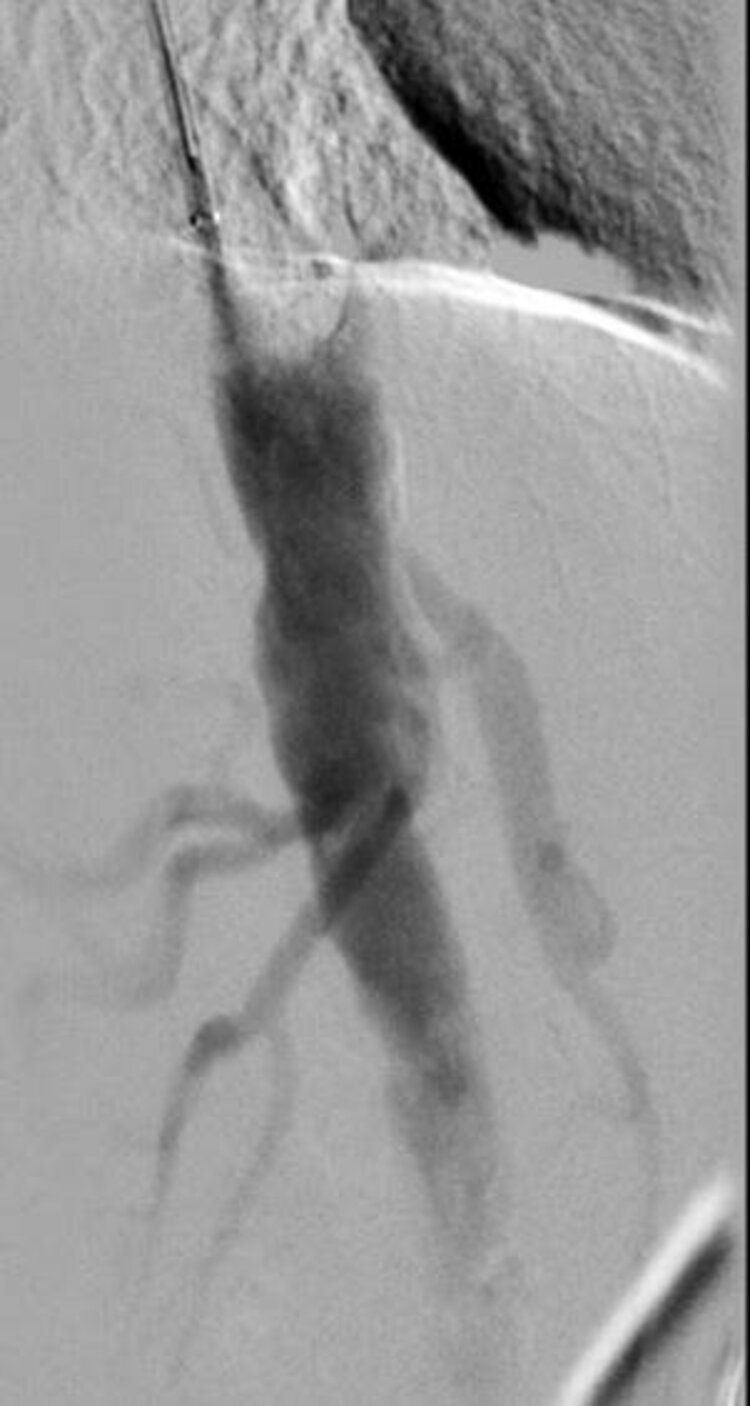

Die Diagnose von Durchblutungsstörungen in den inneren Organen erfolgt in der Regel durch bildgebende Verfahren wie Ultraschall, Angiographie oder CT-Scans.

Die Behandlung kann je nach Schweregrad und Ursache variieren und umfasst in der Regel Medikamente und/oder interventionelle Verfahren wie die Stentimplantation oder Operationen, um den Blutfluss wiederherzustellen.